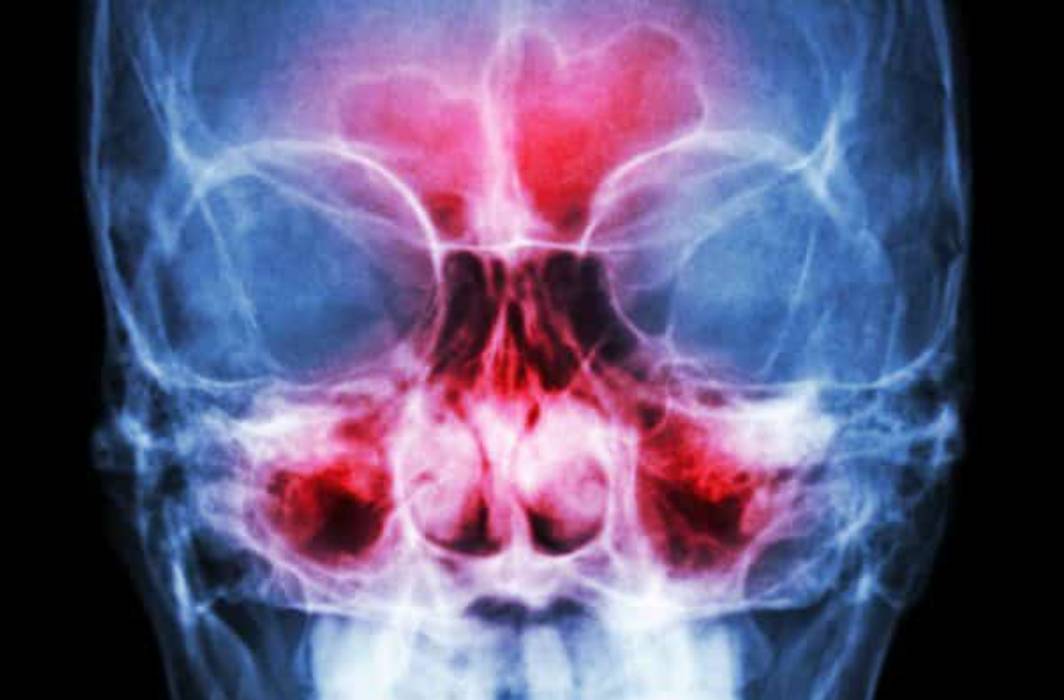

Sinusitis is an inflammation of the nasal passages that prohibits mucus from draining properly. It is considered chronic when it persists for 12 weeks or longer and doesn’t respond to medical treatment. Chronic sinusitis is the single biggest chronic health condition in the U.S., affecting some 37 million Americans annually.

Chronic sinusitis is often the result of infection. Colds and allergies may lead to an abundance of mucus that blocks the sinuses, causing irritation and swelling and allowing bacteria and other germs to grow. Other factors that can cause chronic sinusitis include a deviated nasal septum, nasal polyps, tumors, complications from autoimmune disorders and trauma to the face or head.

In order to diagnose chronic sinusitis, your doctor will examine you and ask questions about your symptoms and medical history. Your doctor will visually inspect your nose for polyps and other obstructions. Your doctor may also use a nasal endoscopy or a CT scan for a more in-depth look.